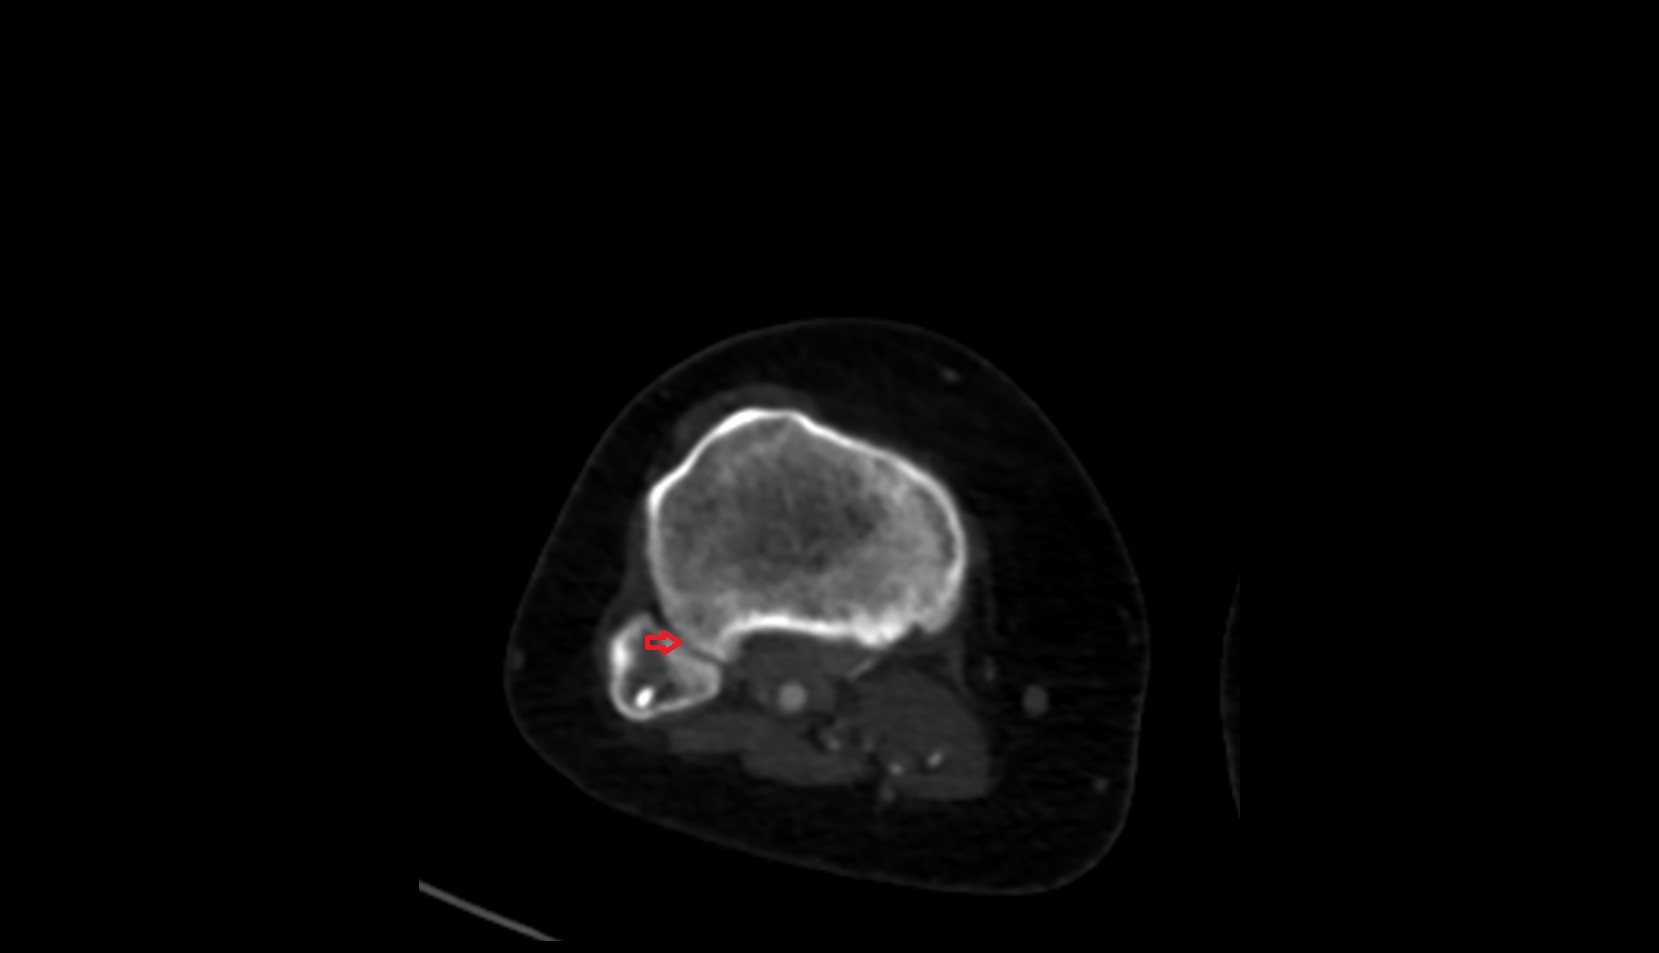

- Elbow joint

- Head of radius

- Neck of radius

- Olecranon

- Coronoid process of ulna